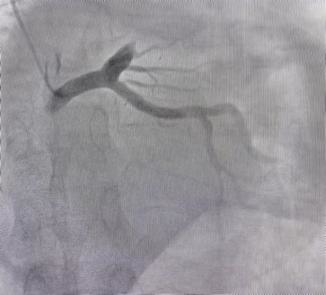

迅速完成穿刺并顺利送入造影导管后,造影结果却给术者一个大大的难题:患者前降支近段完全闭塞,开口近段瘤样扩张,直径约6-7mm,几乎就是正常人的两倍。快速通过导丝,执行血栓抽吸操作,血管得以重新畅通。然而病变位于真分叉处,第一对角支的直径仅约3.5mm,且开口处有高达90%的狭窄。面对这一情况,精准的治疗方案依赖于丰富的经验分析:是采用单支架策略?还是双支架?或者尝试球囊拘禁技术?但主支直径过大,无合适支架。李绍波主任经过短暂快速地思考后,决定使用药物球囊!

(闭塞病变前瘤样扩张改变)